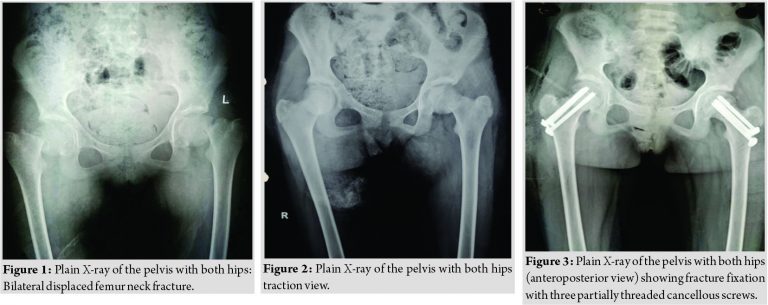

Introduction and patient information: An 11-year-old girl was brought to pediatric emergency for the assessment of fever with generalized tonic-clonic seizures and inability to walk. Her serological evaluation revealed hypocalcemia and hyperphosphatemia (Table 1). Workup for fever was normal which subsided on antipyretics. Radiological examination of hip showed bilateral displaced femur neck fracture (Fig. 1, 2).

She was started on oral calcitriol 0.75 μg thrice daily and oral calcium, and after 3 weeks of therapy, her serum calcium levels had risen to 9.2 mg/dl, and serum phosphorus and alkaline phosphatase levels had fallen to 6.2 mg/dl and 238 IU/L, respectively. The level of PTH remained grossly elevated (240 ng/L). Therapeutic interventions: The patient was managed with bilateral skin traction till normalization of biochemical profile. After correction of biochemical profile, fracture was managed with closed reduction and fixation with three partially threaded cancellous (PTCC) screws about 3 weeks after trauma [5] (Fig. 3, 4) On traction table under spinal and epidural anesthesia, both the fractures were reduced by closed reduction under fluoroscopic guidance and 3 mm × 6.5 mm partially threaded cannulated cancellous screws were inserted in inverted triangle fashion. Reduction was reconfirmed under C-arm.